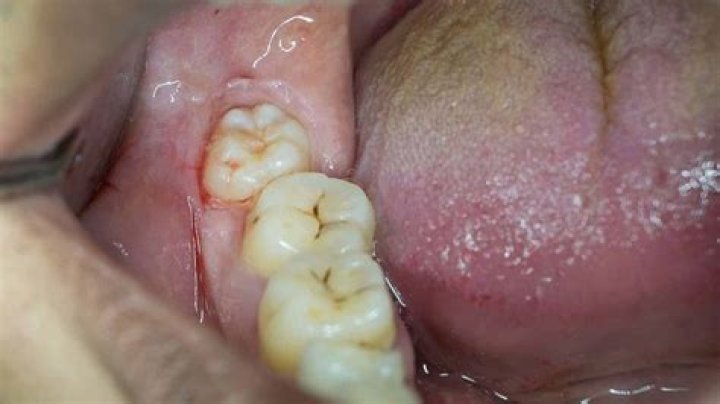

What does wisdom teeth coming in feel like?

Even if your wisdom teeth emerge through your gums normally, they can cause you to feel various mild symptoms. You might experience some mild pain, the feeling of pressure in your mouth or jaw, or a dull throbbing sensation in your gums, close to the opening of your throat or in your jaw bone which is nearby.

How do I know if my wisdom teeth are coming in correctly?

If your wisdom teeth are growing in properly, you won't feel any significant pain or discomfort near the rear of your mouth. If you do, this could be a sign that your wisdom teeth are coming in improperly, or are becoming infected – and you should have them pulled right away.